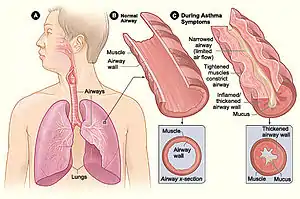

Asthma is the result of chronic inflammation of the conducting zone of the airways (most especially the bronchi and bronchioles), which subsequently results in increased contractability of the surrounding smooth muscles. This among other factors leads to bouts of narrowing of the airway and the classic symptoms of wheezing. The narrowing is typically reversible with or without treatment. Occasionally the airways themselves change.[22] Typical changes in the airways include an increase in eosinophils and thickening of the lamina reticularis. Chronically the airways' smooth muscle may increase in size along with an increase in the numbers of mucous glands. Other cell types involved include T lymphocytes, macrophages, and neutrophils. There may also be involvement of other components of the immune system, including cytokines, chemokines, histamine, and leukotrienes among others.[21]